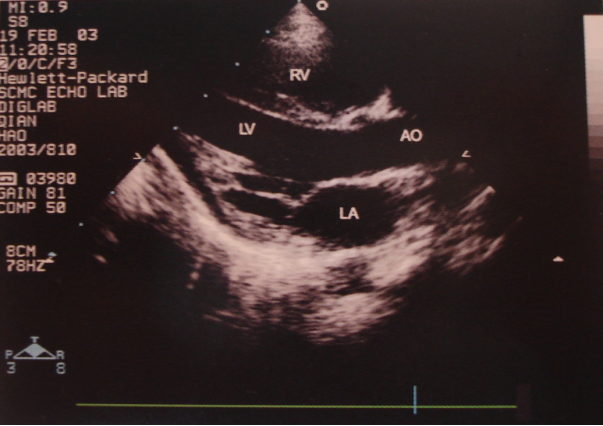

M型超声心动图

二维超声心动图

胸骨旁长轴切面 四腔心切面